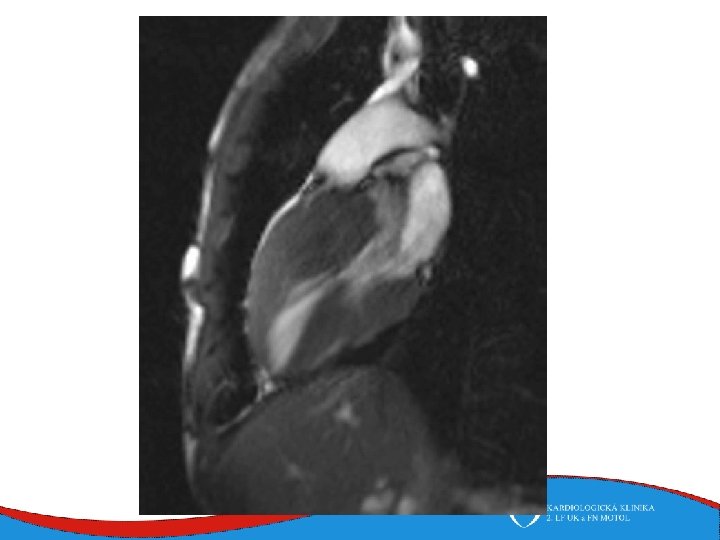

Diagnosis Family history Phisical examination ECG systolic murmur at the apex and lower left sternal border heterogenous LVH, patol. Q , QS, …. ECHO – golden standard MRI septal thickness more than 15 mm, papillary muscles hypertrophy, mitral anterior leaflet elongation, pressure gradient regions of myocarrdial fibrosis regions of late gadolinium enhancement (LGE) Stress test blood pressure responce ECG monitoring ventricular arrhythmia Selective coronarography

Left ventricular non-compaction • Signs and symptoms • Heart failure • Thromboembolic complications • LV trabecularization- predisposition • Anticoagulation therapy (systolic dysfunction) • DG – echo, MRI • Therapy – heart failure therapy, anticoagulation therapy

Tako-tsubo